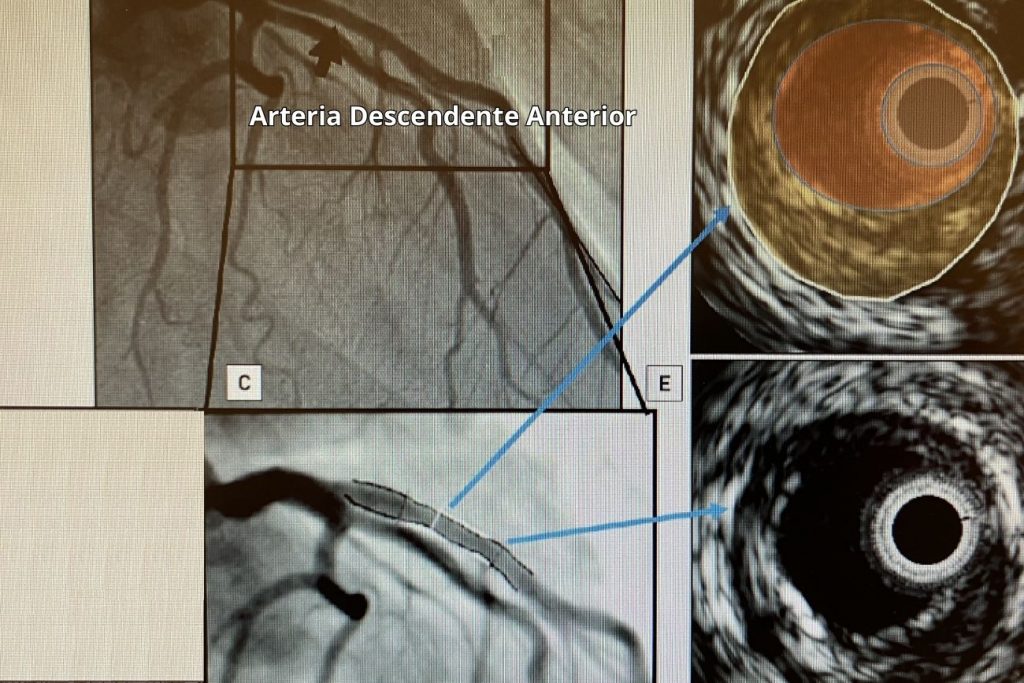

Las imágenes intracoronarias por medio del ultrasonido (IVUS) proveen información de gran utilidad, que es usada en la práctica médica para optimizar el implante de los stents coronarios y minimizar las complicaciones relacionadas a su utilización.

La angiografía muestra las arterias como una luz plana con contraste, no permitiendo evaluar la pared de la arteria y comparando los segmentos enfermos (obstrucciones) con segmentos supuestamente sanos. Por el contrario, el ultrasonido intravascular (IVUS) en escala de grises puede evaluar completamente la extensión de la enfermedad tanto en forma axial como longitudinal.

“Las evaluaciones previas al procedimiento de angioplastia, permiten obtener las dimensiones reales de la luz arterial y del vaso, y las características propias de las obstrucciones (calcificación) así como la extensión de las mismas” explica el Dr. Guillermo Pacheco, jefe del Servicio de Hemodinamia, Angiografía y Cardiología Intervencionista del Sanatorio Allende y añade: “Esto facilita la posibilidad de dimensionar el tamaño óptimo del stent y guiar la estrategia más adecuada para su implante. Las disecciones de los bordes, el prolapso de la placa a través de la malla del stent, la posición incompleta del stent se evalúan seguramente mediante IVUS”. La reestenosis del borde, el prolapso de la placa, la fractura o aposición incompleta del stent se evalúan fácilmente mediante IVUS.

El equipo IVUS consta de un catéter que incorpora un transductor miniaturizado y una consola para reconstruir y visualizar la imagen. Estos se introducen por dentro de catéteres guías de mayor dimensión y tienen la capacidad de mostrar el flujo sanguíneo en color (según los equipos) para facilitar la distinción entre los límites de la luz y la pared del vaso sanguíneo.